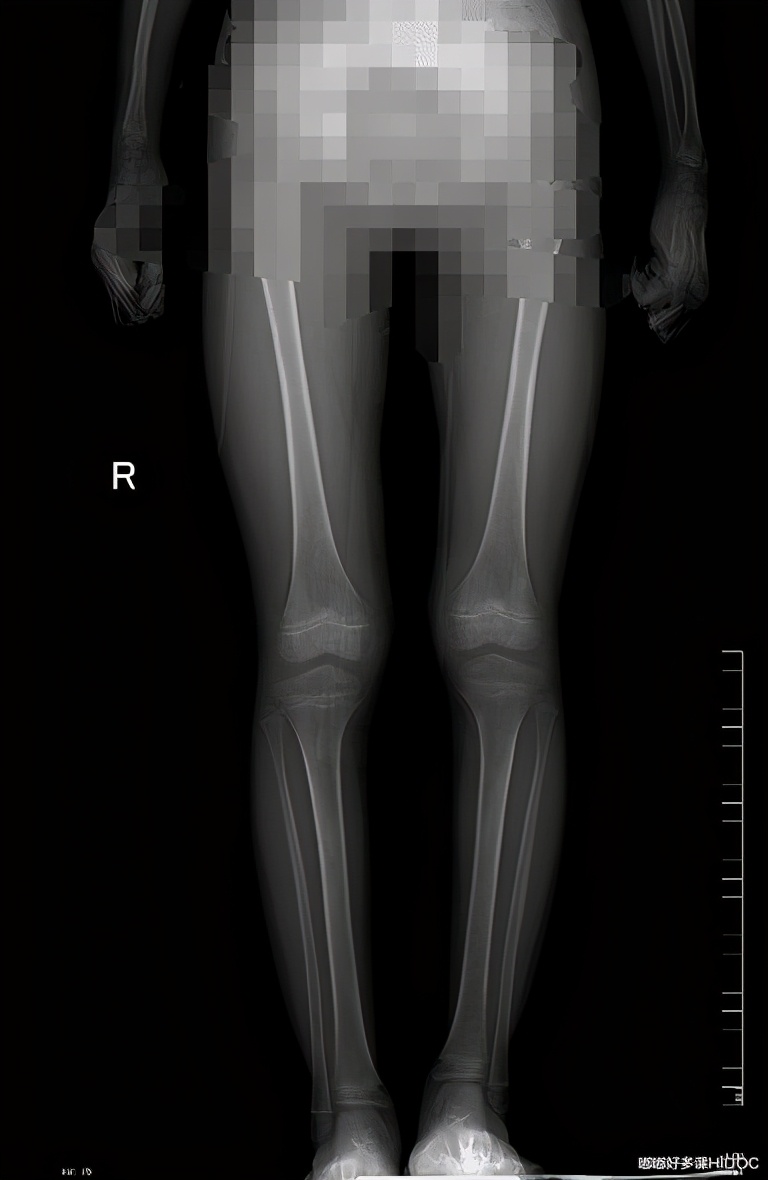

由两条腿不等长引发的脊柱侧弯,发现病因可以骨科矫正。此例孩子两条腿不等长,拍片看得很清楚,肉眼来看并不明显。若家长怀疑孩子可能存在此类问题,可到医院拍片检查。

- 你的一条腿比另一条短吗?Y/N